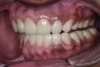

The authors report on a 21-year-old patient who presented with severe discoloration and mild sensitivity of teeth (Figure 1). The teeth visible in his smile were very short, unsightly, and unbecoming for his age.

A thorough clinical examination and analysis were carried out to assess the esthetic and functional problems of the patient (Figure 2 through Figure 7). The medical history was non-contributory, except for mild leukoderma. Temporomandibular joint (TMJ) function was within normal range.

Figure 2. Preoperative 1:2 retracted frontal view.

Figure 2

Figure 3. Preoperative 1:2 retracted right lateral view.

Figure 3

Figure 4. Preoperative 1:2 retracted left lateral view.

Figure 4

Figure 5. Preoperative 1:1 retracted frontal view.

Figure 5